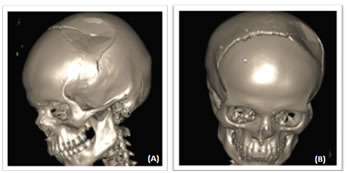

Figure 3: CT 3D reconstruction in a 15-year-old girl revealed (A) depressed fracture of left frontoparietal bone (blue arrow). (B) Coronal suture diastasis in the same patient (Red arrow)